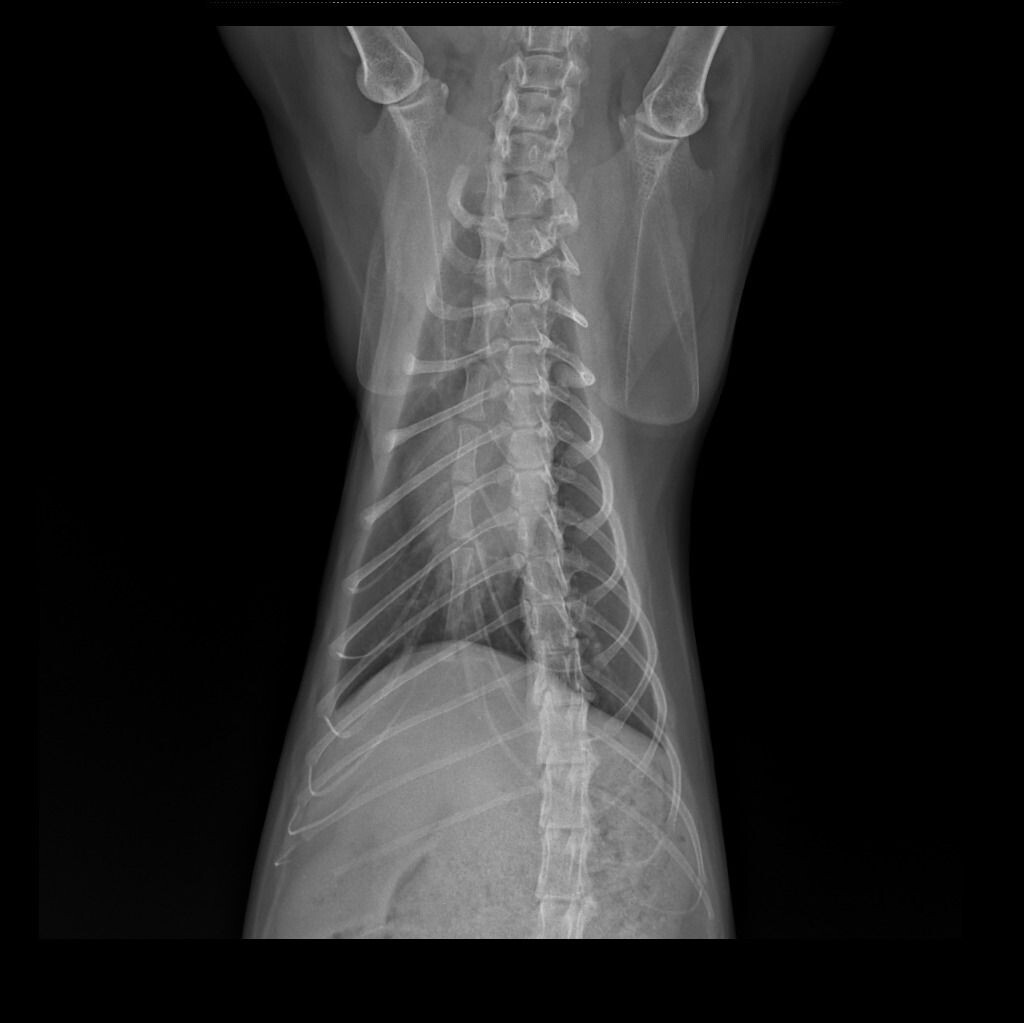

Мы прошли несколько курсов поддерживающей терапии

. В мае кошечка стала тяжело дышать, с приствистом. Меня это напрягло. Сделали рентген. Метастазов в легком нет.

На данный момегт кошеска живет обычной жизнью. Как видно по фото , она не худая, не изможденная. Челюсть удалось уменьшить. Кушает хорошо, может сухой корм кушать, дыхание ровное. К сожалению, санацию полости рта проводить нельзя, неизвестно, как отреагирует опухоль.

Фото снимков рентгена прилагаются.